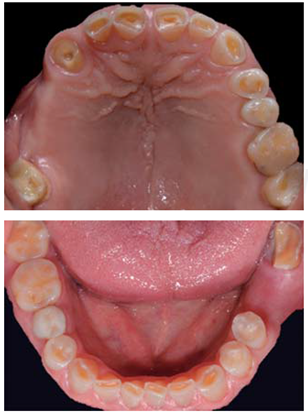

Este reporte documenta el tratamiento de un paciente masculino de 68 años de edad. Comenta tener dificultades masticatorias y digestivas debido a importante desgaste dental, se dice incómodo al sonreír; no refirió padecimientos sistémicos, fumó durante ocho años, diagnosticado con hipertensión arterial controlada. Se observa atrición generalizada, ausencia de dientes 14, 15, 16, 46 y periodonto sano (Figuras 1a4). Los dientes 13 y 37 presentaban tratamiento de conductos y periápice sano, sin restauración (Figura 5).

Para cuantificar la reducción de DVO, se examinó el perfil facial y la estética mediante análisis fotográfico y vídeo (Figuras 6y7). Además de realizar un cuidadoso análisis del montaje de los modelos diagnósticos en articulador semiajustable (Figura 8). También se examinó el esquema oclusal (presentaba relación borde a borde) y la estructura dental con la que se contaba (Figura 3). La revisión dinámica fue clave para determinar que el paciente exhibe una línea de sonrisa alta (Figura 9).